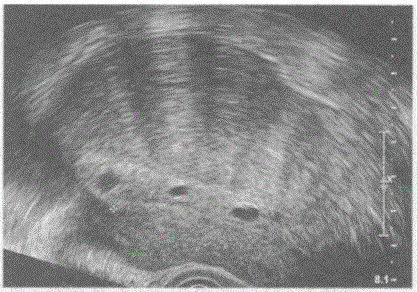

问题 临床资料:女,42岁,自述月经不规律4年余,阴道出血,诊刮清宫半年后复查。 超声综合描述:经阴道扫查子宫前位,增大,子宫内膜不均匀增厚前移,厚度1.4cm,可见多个小无回声区,子宫前壁厚度1.4cm,后壁厚度4.8cm,回声明显不均。 超声提示:

选项 A.葡萄胎 B.子宫腺肌症子宫内膜息肉 C.子宫增大子宫腺肌症子宫内膜增生 D.子宫肌瘤

答案 C